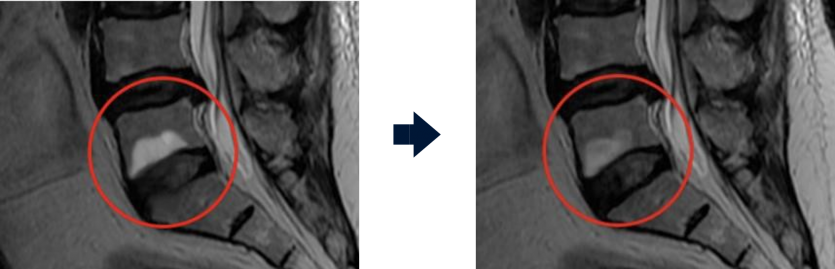

Before the procedure After the procedure

Neuroplasty improves the problem of drugs not reaching the lesion and flowing out due to adhered discs and nerve inflammation. It confirms the exact lesion site through real-time imaging and directly injects the drug to eliminate adhesions and relieve inflammation.